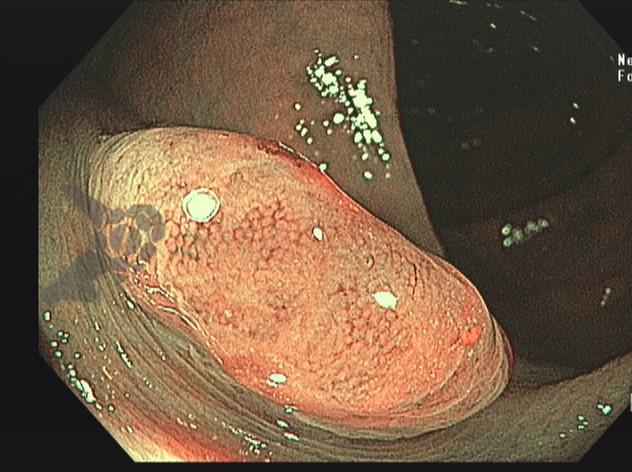

A TVNA é uma técnica de punção por agulha fina em que a agulha atravessa um vaso sanguíneo interposto (como a aorta, artéria pulmonar ou veia cava) para alcançar uma lesão torácica ou abdominal.

Técnica passo a passo:

- Avaliação prévia com imagem (TC ou RNM)

- Estudo cuidadoso com doppler

- Evitar vasos com calcificação ou aneurismas

- Escolher agulhas finas (FNA 25G ou 22G)

- Preferir técnica com ROSE, se disponível

- Após punção, monitorar área por 2 minutos com doppler

- Observação clínica de 6 horas à 24 horas